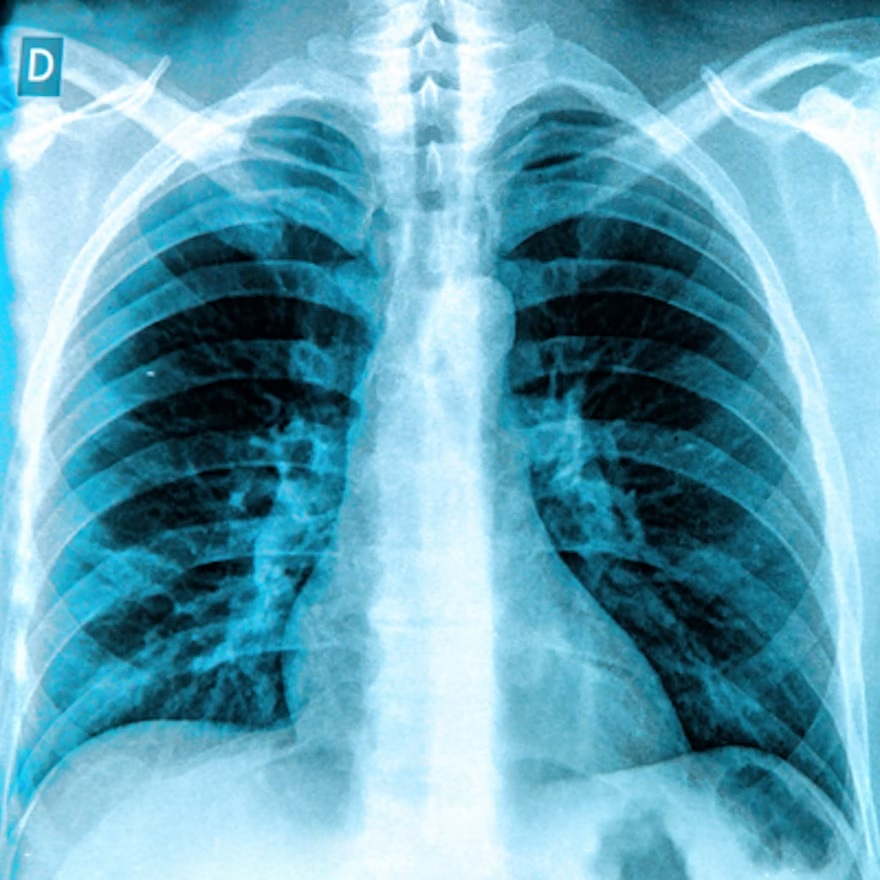

Attenuation-based (left) and dark-field (right) posteroanterior radiographs of the thorax in example subjects. Images were obtained in (A, B) a 33-year-old man and (C, D) an 81-year-old man. The same window and level settings were applied within the respective modality. While attenuation-based images show attenuating structures, such as the bones and the soft tissue, dark-field images show the amount of tissue interfaces in the beam path. Image courtesy of Radiology."Because of the nature of signal generation in dark-field imaging, bone structures and soft tissue generate only a minimal dark-field signal compared with lung tissue. This feature allows for a detailed depiction of lung tissue without impairment by surrounding structures. We found that the quantitative x-ray dark-field coefficient based on the total dark-field signal and lung size is independent from the subject's characteristics," the researchers wrote.